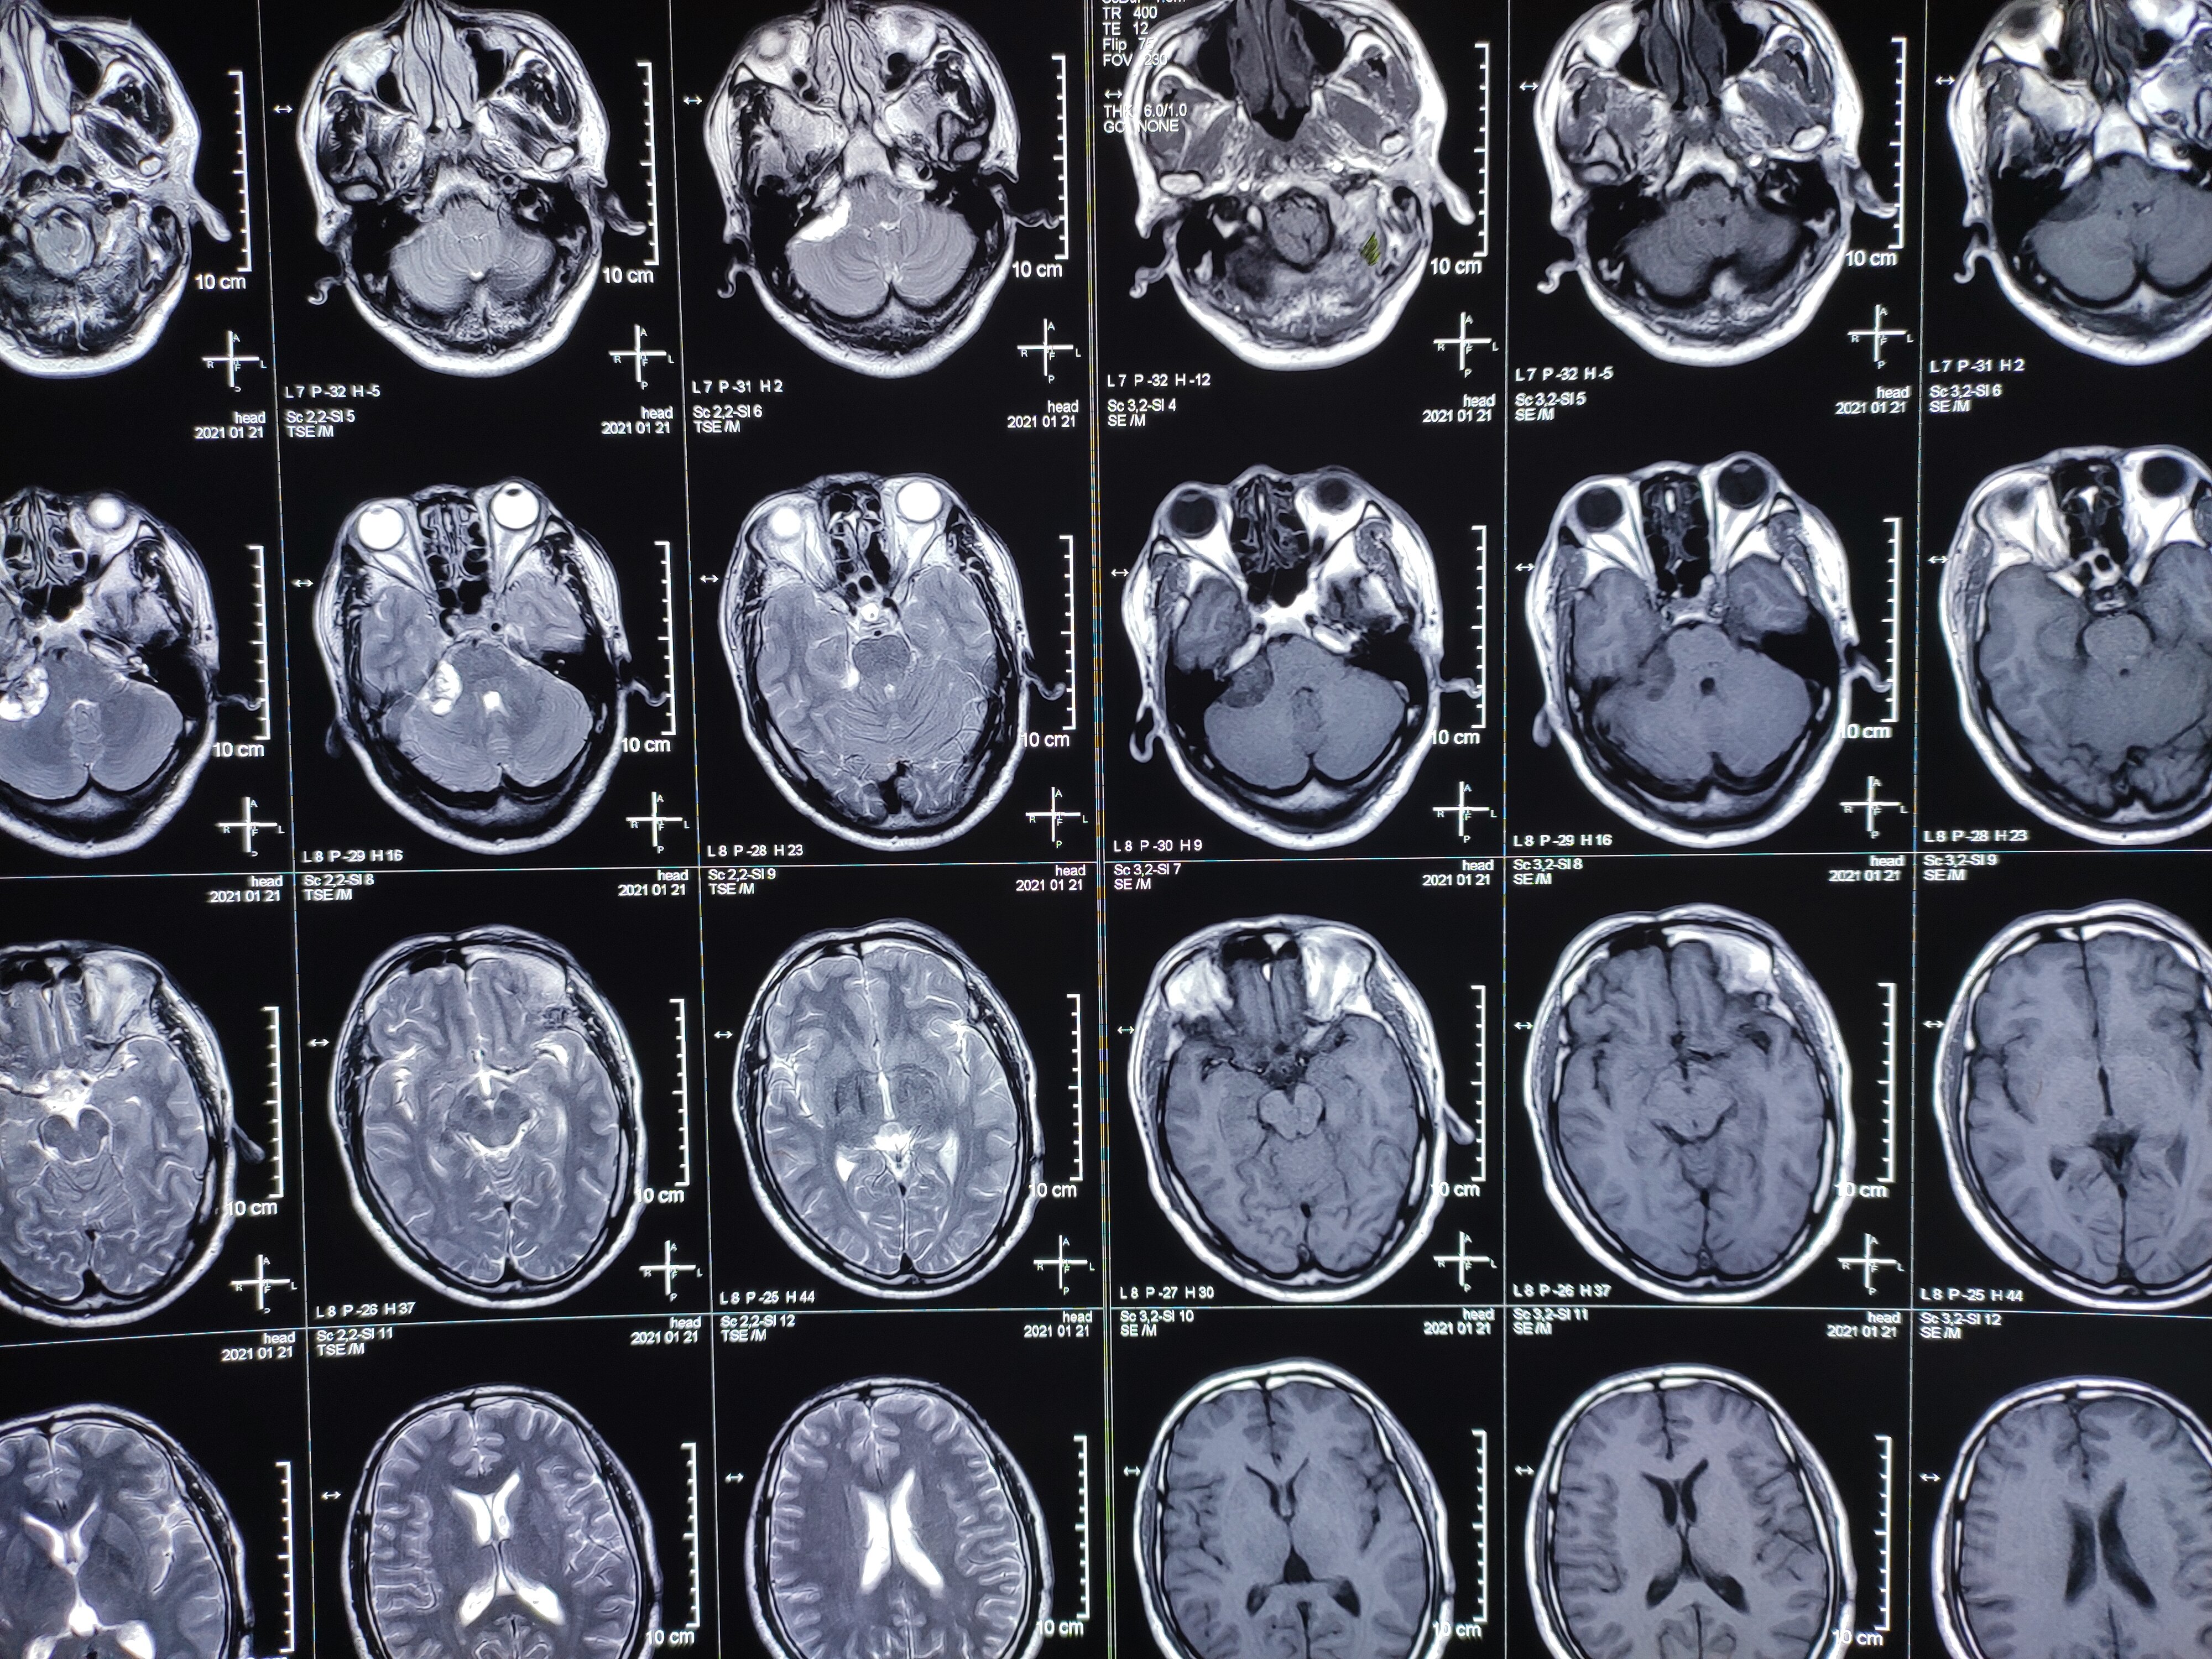

术前头颅mri 增强扫描显示:左侧桥小脑角病灶均一强化,听神经增粗,内

图片尺寸2595x1717